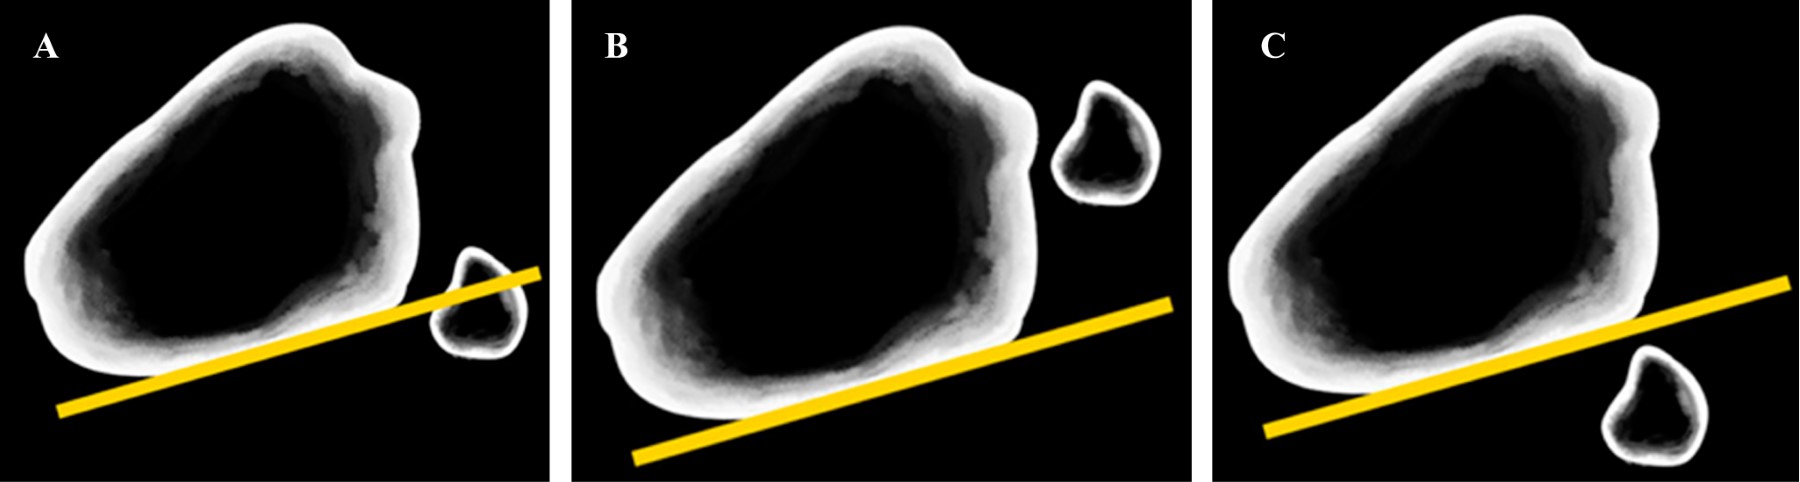

Evaluación imagenológica: frente a un trauma de rodilla, el estudio debe iniciarse con radiografías AP, lateral y axial de patela de la rodilla afectada. En la proyección AP, el aumento del espacio interóseo proximal, visto a través de la ausencia de superposición de la cabeza fibular sobre el margen lateral del cóndilo externo de la tibia sugiere una luxación lateral.15 Sin embargo, la única referencia objetiva descrita en la literatura es la de Resnick y colaboradores que permite identificar una luxación tibiofibular proximal en una proyección lateral.16 Se debe trazar la línea de la cresta posteromedial del platillo lateral de la tibia y evaluar su relación con la cabeza fibular (Figura 3). Se considera fisiológico si esta línea se proyecta sobre la porción media de la cabeza fibular; si la mayor parte de la cabeza se encuentra anterior a la línea de Resnick, traduce una luxación anterior; lo contrario sucede en las luxaciones posteriores.16 A pesar de su constante descripción,2,11,16,17,18,19 no hay estudios que demuestren su sensibilidad y especificidad.

Otro aspecto a evaluar en la proyección lateral es la orientación anatómica de la fíbula. Se han descrito dos variaciones anatómicas: la variante horizontal (menor de 20o de inclinación en el plano horizontal) y la variante oblicua (mayor de 20o), que al tener una menor área de superficie articular predispone a una mayor inestabilidad (Figura 4).11

Para aumentar la precisión diagnóstica y en los casos de permanecer con dudas, se debe complementar con una TC, que aumenta la sensibilidad a 86%.20 En el corte axial se traza una línea por la pared posterior de la tibia que se extiende hacia lateral y se evalúa su relación con la cabeza fibular.20 Si esta línea cruza sobre la mitad anterior de la cabeza fibular, se considera normal (Figura 5); sin embargo, existe variabilidad anatómica de la pared posterior de la tibia, por lo que también se recomienda comparar con la rodilla contralateral.13,20

En resumen, no existe en la actualidad un consenso respecto al orden y al adecuado uso de imágenes al momento de sospechar este tipo de lesiones. Los autores consideran suficiente iniciar, como primera línea, con radiografía AP y lateral comparativas. En el caso de persistir con alta sospecha clínica con radiografías no concluyentes, solicitar una tomografía computarizada (TC) o resonancia magnética (RM) considerando las ventajas y desventajas de cada modalidad. Analizando el caso clínico ilustrado, se evidencia una variante anatómica oblicua en la proyección lateral, la cual apoya el diagnóstico (Figura 1). Por otro lado, complementar con radiografías AP y lateral comparativa y una TC en el ambiente de urgencia hubiese asistido en el diagnóstico. Sin embargo, el paciente se presentó en el servicio de urgencias durante la pandemia de COVID-19, por lo que rechazó la evaluación en agudo con una TC.